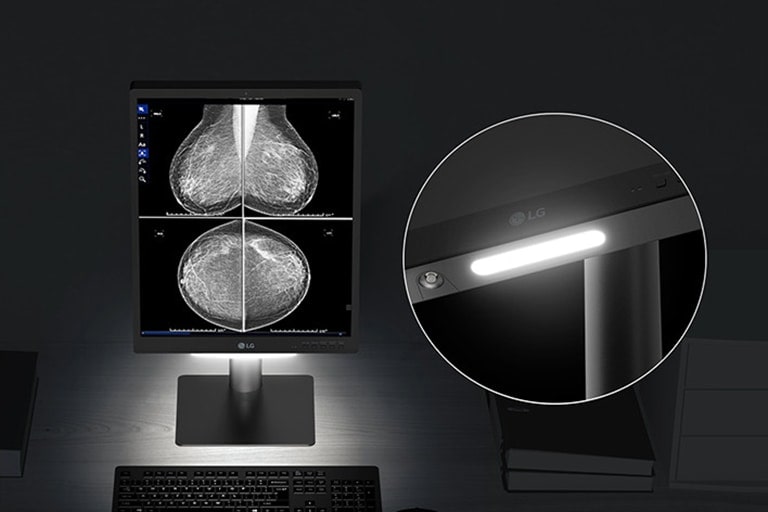

Down light & Wall light

Down light & Wall light

Ideal diagnostic workspace

Down /Wall light mode enhances readability of documents below the monitor even in low-light environments.